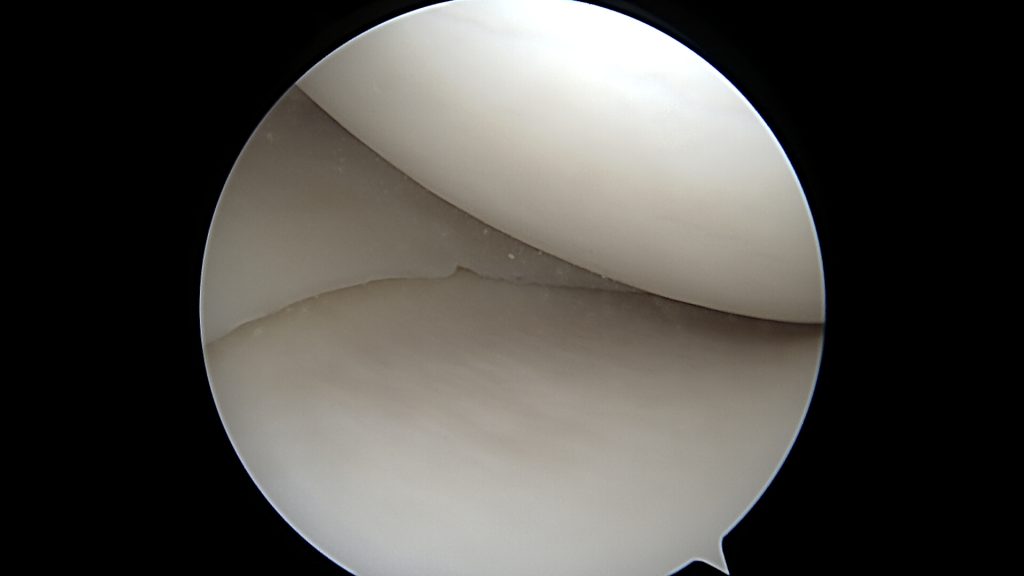

Potwierdzenie rozpoznania tego uszkodzenia następuje podczas zabiegu bardzo szybko. Zaraz po wprowadzeniu optyki do stawu po prostu widzimy łąkotkę nie tam gdzie powinna być, czyli tuż przed kamerą. Po wykonaniu inspekcji wszystkich dostępnych części stawu dokonuje się odświeżenia miejsca uszkodzenia oraz „repozycji” uszkodzonego fragmentu łąkotki (przepchnięcia jej na swoje miejsce). Następnie przy pomocy szwów zakładanych artroskopowo mocują się ją na swoim miejscu.